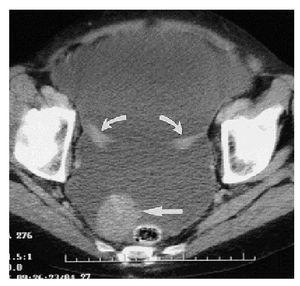

En aproximadamente 75-80% de los casos, el diagnóstico preoperatorio es cáncer de ovario, la evaluación pretratamiento debe incluir una historia clínica completa, la exploración física evaluará la extensión de la enfermedad en la pelvis, posible infiltración rectal, ascitis, "omental cake" y derrame pleural. Los estudios de gabinete deben incluir radiografía de tórax para descartar metástasis, derrame pleural y evaluar el riesgo anestésico. El ultrasonido pélvico y la TAC abdomen/pelvis son de utilidad para evaluar la extensión de la enfermedad. Aunque el diagnóstico de cáncer primario de peritoneo no puede ser realizado en el preoperatorio, se puede sospechar cuando los estudios radiológicos revelan la evidencia de carcinomatosis con ovarios de tamaño normal (Imagen 1). En un estudio de 36 mujeres con carcinoma primario de peritoneo, la TAC preoperatoria reveló ascitis (80%), afectación de epiplón (78%), engrosamiento de peritoneo (61%), pared de sigmoides engrosada (28%), derrame pleural (30%) y ovarios de tamaño normal (85%)17,18,19 (Imagen 2).

Imagen 1. TAC pelvis: ascitis, implantes peritoneales.

Imagen 2. TAC pelvis: ascitis, implantes peritoneales y ovarios de tamaño normal.